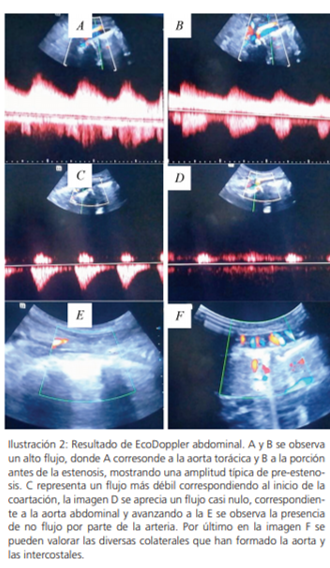

A continuación, se realiza ecografía Doppler abdomino-pélvica el mismo que reporta 1. Obstrucción total de la aorta abdominal en su tercio medio; con la presencia de varias anastomosis intra-abdominales y en pared abdominal que irrigan las arterias ilíacas y pélvicas; con flujos de tipo post-obstructivo (Parvus-Tardus). 2. Flujo de aorta abdominal proximal tipo postestenótico (Tardus- Parvus); por lo que recomiendan Angio-Tac aorto-abdomino pélvica.

Se realiza Angiotac toraco-abdominal encontrándose disminución de calibre de arteria pulmonar izquierda en el tercio medio; a nivel de aorta ascendente dilatación de 40x 42mm, a nivel de cayado aórtico diámetro de 25mm, por debajo de emergencia de arteria subclavia izquierda 17 x 14.6 mm, conforme desciende se observa disminución de calibre de luz hasta T9, a nivel de T12 pérdida total de la luz de vaso que se re canaliza a través de abundante irrigación colateral. A nivel infra renal aorta marcadamente adelgazada de 6mm, así como las arterias iliacas; arterias renales severamente disminuidas, derecha 3.6mm, en riñón izquierdo se aprecian dos vasos de 2.2 y 2.5mm.